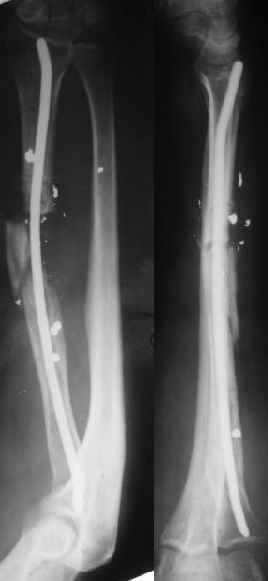

Пока мы наложили аппарат для восстановления оси и длины лучевой кости. Снимок прлагаю.

Спасибо за снимки, один только вопрос-

Почему отказался от одномоментной дистрации в аппарате и штифтования?

Снимок сделан после выбирания люфта в аппарате, то есть уже создано приличное дистракционное усилие. Даже пытаться дальше рвать одномоментно не стали.

Спасибо за присланную рентгенограмму после операции. На мой взгляд, было бы неплохо провести еще одну или даже две спицы с упором через промежуточный отломок с противоположной к введенной через дистальный отломок спице с упором.